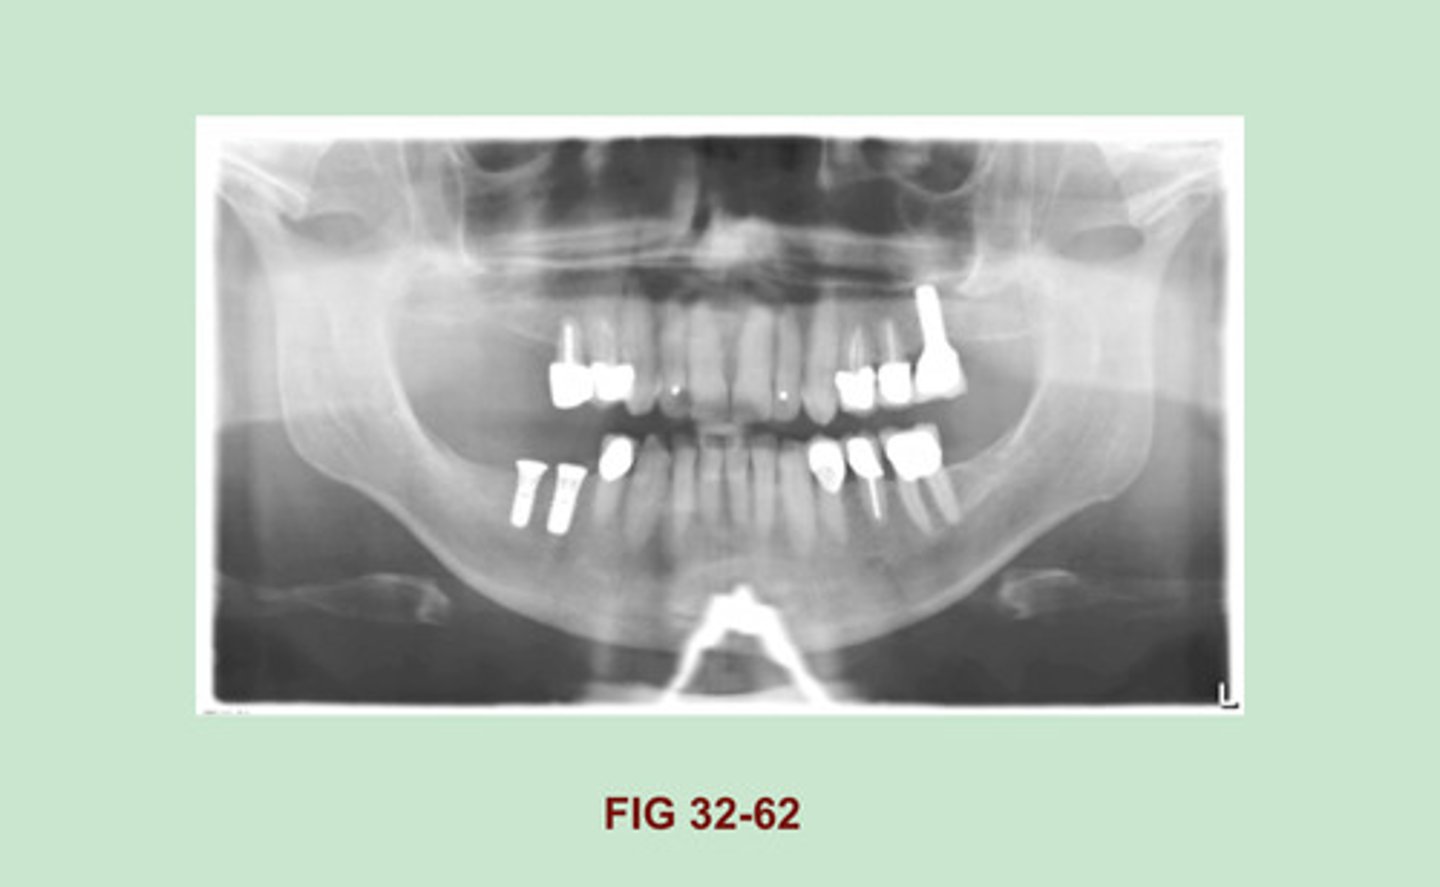

Identify the RADIOPACITY seen in the MIDDLE of this PANORAMIC IMAGE OBSCURING the BORDER of the MANDIBLE. (Figure 32-62).

TBA